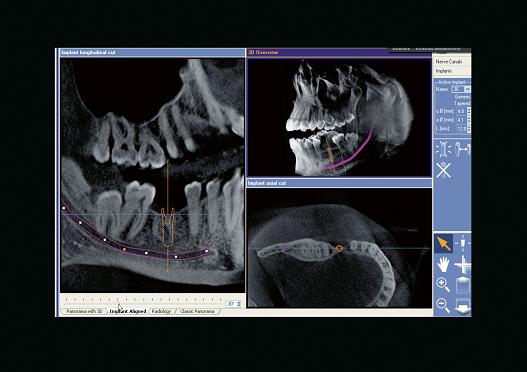

- Программа, выводящая привычные стоматологам панорамные снимки с интуитивным трехмерным управлением объемом и абсолютно новыми возможностями диагностики.

Совершенная диагностика с GALILEOS и GALAXIS

После прохождения короткой реконструкции GALILEOS показывает не только 3D-изображения отличного качества. Большой объем с высоким разрешением деталей отображается при панорамной, цефалометрической и TSA-съемке. Привычный панорамный снимок позволяет интуитивно ставить диагноз в масштабе реального времени.

Новая, интегрированная в SIDEXIS XG программа GALAXIS уверенно ведет пользователя в будущее диагностики.

Надежная 3D-диагностика

В 3D-объеме GALILEOS (15х15х15) см3 на панорамном и цефалометрическом снимке можно интуитивно переходить из одного окна в другое и обследовать различные зоны.